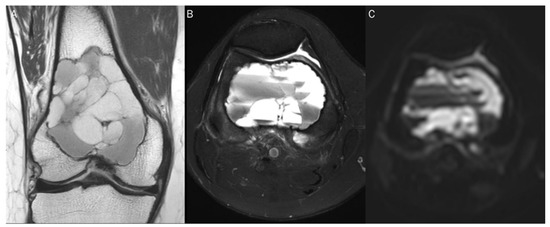

7.1. Cyst

| Benign cyst | T2 shine-through | Free water |